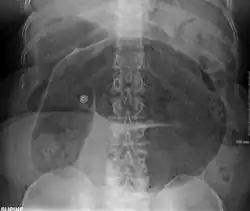

- Abdominal x-ray – tire-like shadow arising from the right iliac fossa and passing to the left

-

Coffee bean sign in a person with sigmoid volvulus -